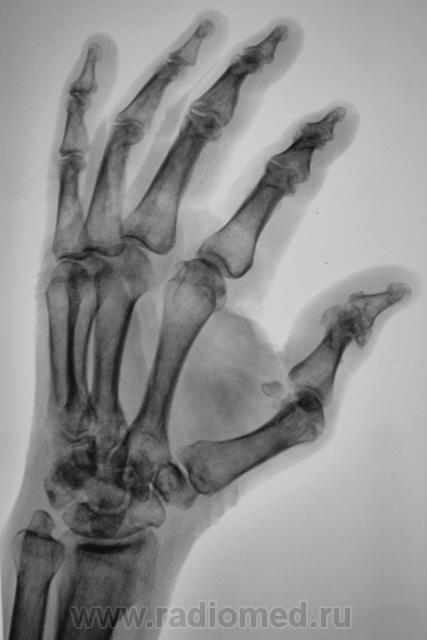

Травма. Есть перелом или нет перелома?

Игра теней. Нет перелома. Хотя без клиники трудно судить.

Ни первого, ни второго. По-моему.

Вроде нет, Но я бы посмотрел на увеличенном изображении эпифиз 1 пясной.